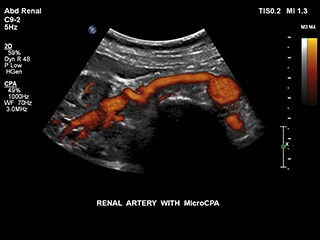

Bisher war die Erfassung von Flussdaten bei kleinen Gefäßstrukturen mit niedriger Flussrate schwierig. Die neue EPIQ Funktion MicroCPA bietet eine schnelle und einfache Darstellung von Mikrozirkulation mit niedriger Geschwindigkeit und ermöglicht eine hohe Diagnosesicherheit bei der Beurteilung der Organperfusion oder von kleinen Gefäßbetten.